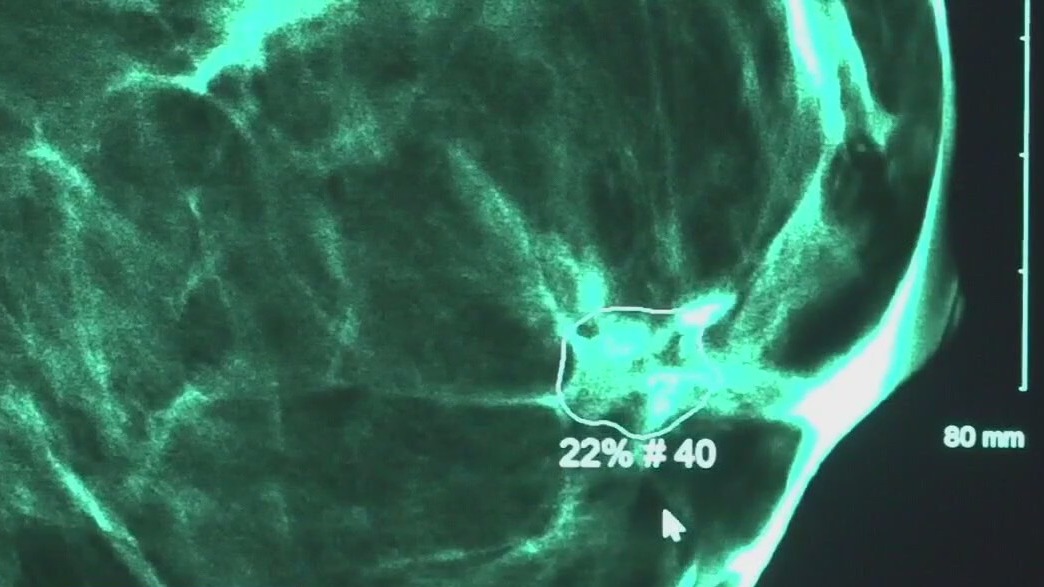

Austin doctor discusses breast cancer risk assessment that helped actress

Actress Olivia Munn revealed she was diagnosed with breast cancer and underwent a double mastectomy last year.

Olivia Munn diagnosed with breast cancer

The 43-year-old actress has been battling the disease since April 2023.